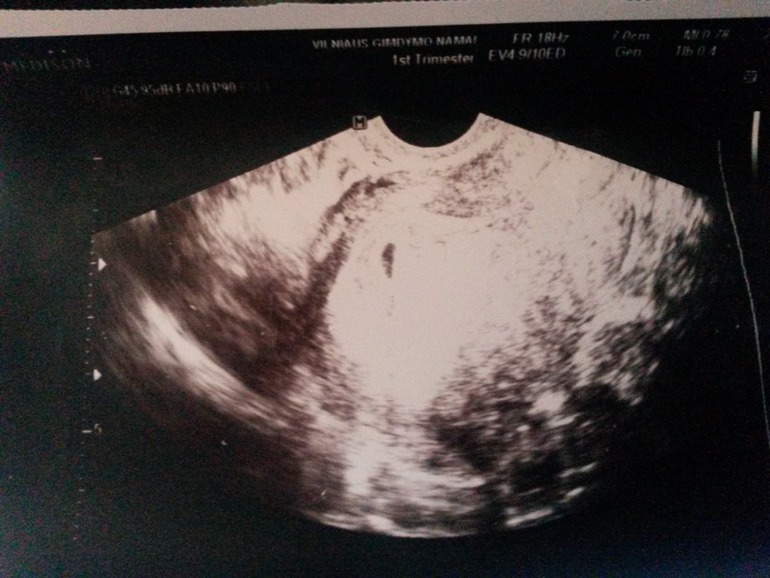

Вот узи. Плодное яйцо изза тонуса дефармируется. Оно должно быть кругленькое у меня овальное и тонкое. Боженьки помаги мне и моей крошке.

Пришли анализы. Прогистерон упал на 10 нмоль единиц. (Был 68- стал 58,8) Хгч вырос с 656 до 2683). Начинаю пить гормоны и лежу. По узи видно сто изза тонуса плодное яйцо сжато. Должно быть кружок к меня овал. Большая вероятность выкидыша.